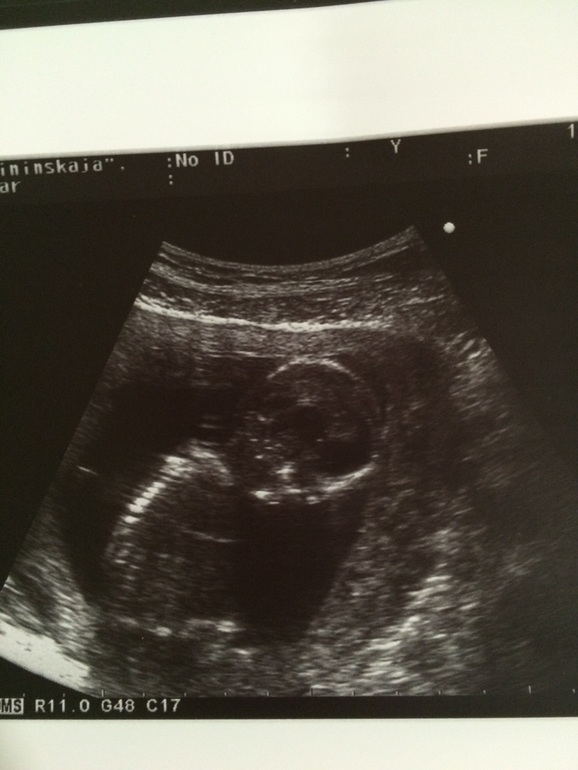

Шевелюшки, икотаВсем привет! Вот и у меня настал этот радостный момент. Моя малявочка в животике ходуном ходит!!! И это не кишечник, абсолютно другие ощущения! Непередаваемые! Как будто шарик в животе перекатывается потихоньку. Особенно чувствуется когда на боку лежишь. Вчера была на УЗИ, ходила для себя так как 2 дня назад набегалась по дому и живот начал немного покалывать (но шпа и папаверин сделали свое дело быстро). Далее под кат)))) Врач нам сообщила, что все в норме, развитие на 15-16 недель и вот-вот должна уже чувствовать шевеления. Матка уже высоко и большая, вроде так сказала. Мы весим 130 грамм, большие уже, по сравнению с прежним узи. Ляля моя сидела поджав ножки и упорно не хотела переворачиваться, короче кто там у нас так и не видно. А руками во всю машет!!!! В общем все нормально, и тонуса нет тьфу тьфу! Я счастлива)))) а вот и мы